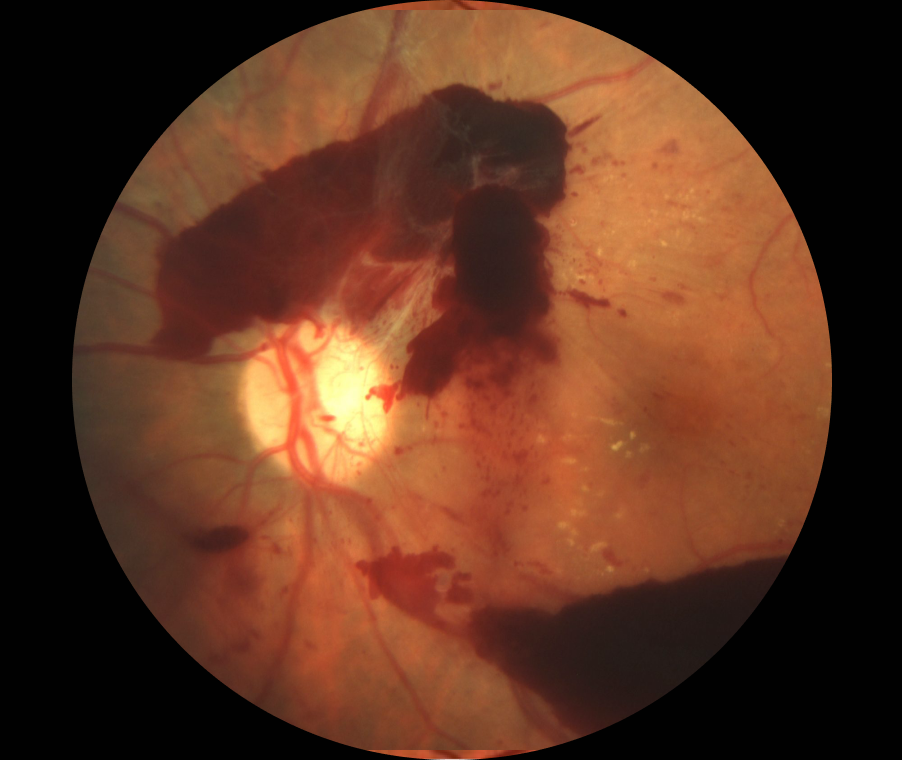

증식성 당뇨망막병증

더 진행된 심각한 단계로 비정상적인 신생 혈관이 형성됩니다. 유리체 출혈, 망막 박리, 녹내장의 위험이 있습니다.